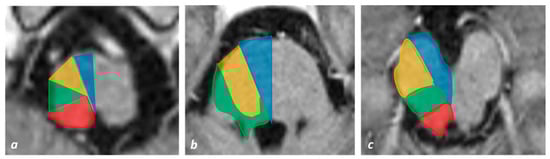

- Venkatesan, P.; Balakrishnan, R.; Ramadoss, K.; Iyer, R.S. Heart appearance sign in pontine stroke: A result of bilateral infarction due to small vessel disease. Neurol. India 2014, 62, 115–116. [Google Scholar] [CrossRef]

- Sen, D.; Arora, V.; Adlakha, S.; Gulati, Y.S.; Doppaladudi, A.; Tiwary, S. The “Heart Appearance” Sign in Bilateral Pontine Infarction. J. Stroke Cerebrovasc. Dis. 2015, 24, e21–e24. [Google Scholar] [CrossRef]

- Tokuoka, K.; Yuasa, N.; Ishikawa, T.; Takahashi, M.; Mandokoro, H.; Kitagawa, Y.; Takagi, S. A case of bilateral medial medullary infarction presenting with “heart appearance” sign. Tokai J. Exp. Clin. Med. 2007, 32, 99–102. [Google Scholar]

- Maeda, M.; Shimono, T.; Tsukahara, H.; Maier, S.E.; Takeda, K. Acute Bilateral Medial Medullary Infarction: A Unique ‘Heart Appearance’ Sign by Diffusion-Weighted Imaging. Eur. Neurol. 2004, 51, 236–237. [Google Scholar] [CrossRef]

- Zhou, C.; He, Y.; Chao, Z.; Zhu, Y.; Wang, P.; Gao, X. The “heart appearance” sign on MRI of Wernekink’s commissure syndrome caused by bilateral caudal paramedian midbrain infarction. Neurol. Sci. 2017, 39, 587–589. [Google Scholar] [CrossRef] [PubMed]